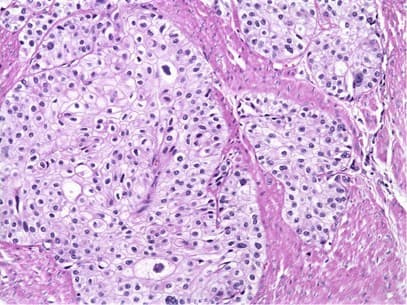

Automated cancer cell screening platform

Cancer Histology AI

Owkin

Diagnostics tool for Big Pharma